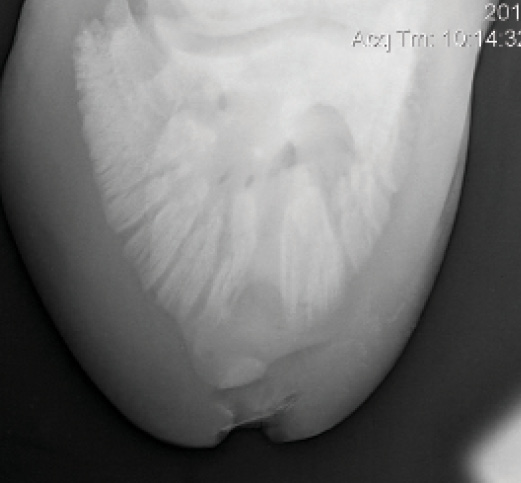

Through examination and radiographs, Bras found that the horse had two keratomas (Figure 1 Above) in the left hind foot. Two masses, one at the lateral toe (Figure 2) and one directly below P3 in the region of the sole lesion (Figure 3), can be seen in radiographs. Keratomas classically show up on radiographs as a radiodense (white) circle or semi-circle outlined by a radiolucent (dark) margin. The presence of both the cylindrical keratoma under the dorsal hoof wall and the spherical keratoma beneath the sole presented a problem for Bras.

Figure 3